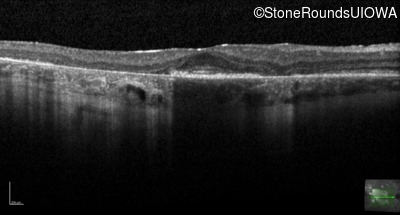

Age at visit: 30 years

This 30 year old man first noticed poor vision in dim light when he was five years old. His visual acuity began to fall in his early 20's.

Macular Disease WDR19 His344Arg CAT>CGT Ser485Ile AGT>ATT AR